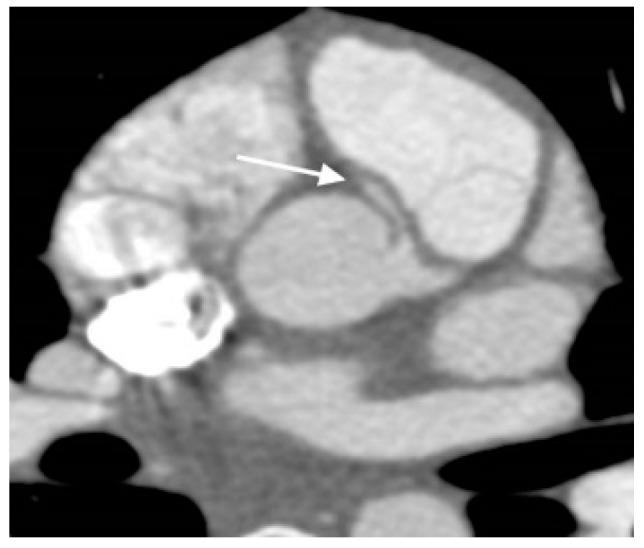

多模态成像与心脏科-放射科先天性心脏病接口入门

A Primer on Multimodal Imaging and Cardiology-Radiology Congenital Heart Interface.

Pediatric cardiology imaging laboratories in the present day have several modalities for imaging of congenital and acquired cardiovascular disease. These modalities include echocardiography, cardiovascular magnetic resonance imaging, cardiac computed tomography and nuclear imaging. The utility and limitations of multimodal imaging is described herein along with a framework for establishing a cardiology-radiology interface.

当今的儿科心脏病学影像实验室拥有多种用于先天性和后天性心血管疾病成像的模式。这些模式包括超声心动图、心血管磁共振成像、心脏计算机断层扫描和核成像。本文描述了多模态成像的效用和局限性,并给出了一个建立心脏病学与放射学接口的框架。